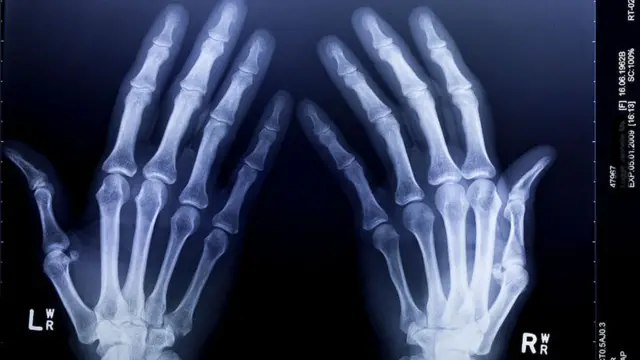

کمبود کلسیم باعث بیماریهای مختلف استخوانی میشود از جمله بیماری راشیتیسم یا نرمیاستخوان در کودکان و استئومالاسی یا نرماستخوانی در بزرگسالان و پوکیاستخوان در سالمندان. بنا بر اعلام سیستم خدمات بهداشت ملی بریتانیا (ان اچ اس) " در سالهای اخیرموارد ابتلا به نرمیاستخوان در بریتانیا افزایش پیدا کرده است، هر چند تعداد مبتلایان هنوز به طور نسبی کم است".

بیش از ۳ میلیون نفر در بریتانیا مبتلا به پوکیاستخوان هستند و بیش از ۵۰۰،۰۰۰ نفر از آنها هرسال به دلیل شکستگیهای درجا (نوعی شکستگی که در آن دو سر استخوان شکسته از هم جدا نشده باشد) در بیمارستان بستری میشوند. عواملی غیر از رژیم غذایی مانند پیشینهٔ خانوادگی، جنسیت، نژاد و مصرف بیش از حد سیگار و الکل و همچنین نداشتن فعالیت بدنی نقش مهمی در میزان ابتلا به پوکیاستخوان دارد.